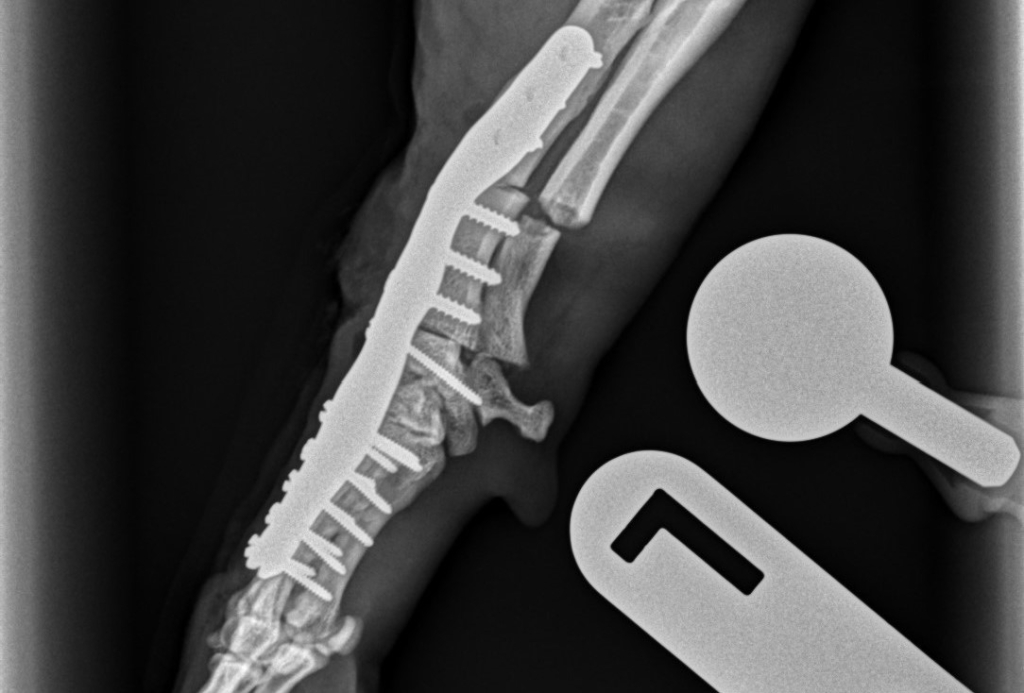

The cause of eight-year-old Basil’s problematic leg and wrist is unknown but had got to the stage where he needed a particularly complicated combination of corrective procedures at Linnaeus-owned Southfields Veterinary Specialists to put it straight and cure the pet’s discomfort.

Among the ‘firsts’ to be carried out by Southfields’ orthopaedic team was the use of a 3D-printed custom-made implant.

Carlos Rubiños, specialist in small animal surgery at Southfields, said: “The operation was challenging as it involved reconstructing and realigning the whole forearm, wrist and paw.

“It’s a rare procedure and this is the first time we’ve used custom-made 3D-printed osteotomy guides and a custom-made metal plate, manufactured by Vet3D.